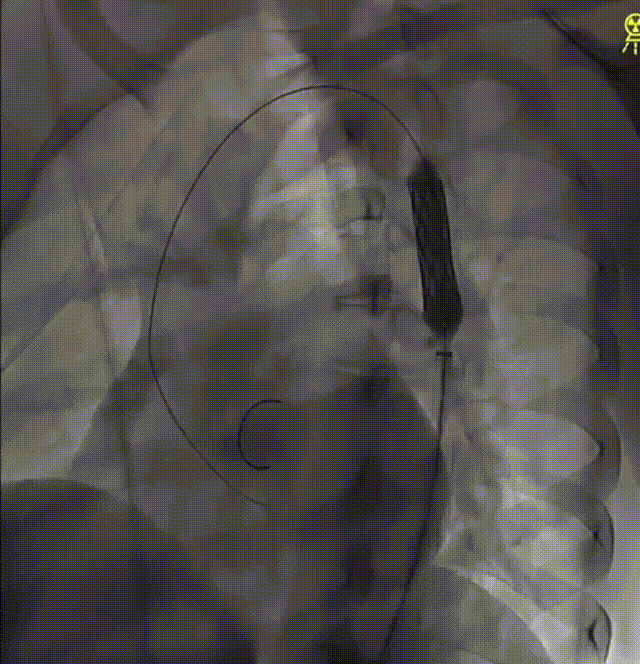

患者男性,86岁,1个月前开始出现夜间阵发性呼吸困难入院。至医院查心电图提示心房颤动,查超声心电图提示二尖瓣前叶(A2偏3区)脱垂并腱索断裂、二尖瓣前叶对合点后移并返流(重度、4级、DMR、Carpentier Ⅱ型)。

术前,宋光远教授团队对患者基本情况进行反复研究,确定患者不适合外科开胸手术,遂决定选择微创的经导管二尖瓣夹合术。术中经股静脉入路,在超声介导下成功完成房间隔穿刺并建立导丝路径。随后,宋光远教授通过信息采集机器人的高清摄像设备清楚展示了MitraClip系统手术器械的准备过程,对Clip、SGC、CDS及固定装置进行排气及体外调试,以及后续的手术过程。由于患者左前降支存在严重狭窄且合并房颤,如何保障患者围手术期血流动力学稳定是完成手术的重要难题。在食道超声及X线引导下,应用两个MitraClip的二尖瓣夹反复调整夹取位置,最终成功捕获并夹合返流严重部位,使二尖瓣在收缩期由大的单孔变成小的双孔,从而减少二尖瓣返流。二尖瓣夹释放后,超声显示返流几近消失,患者各项生理指标正常。

术前彩超结果